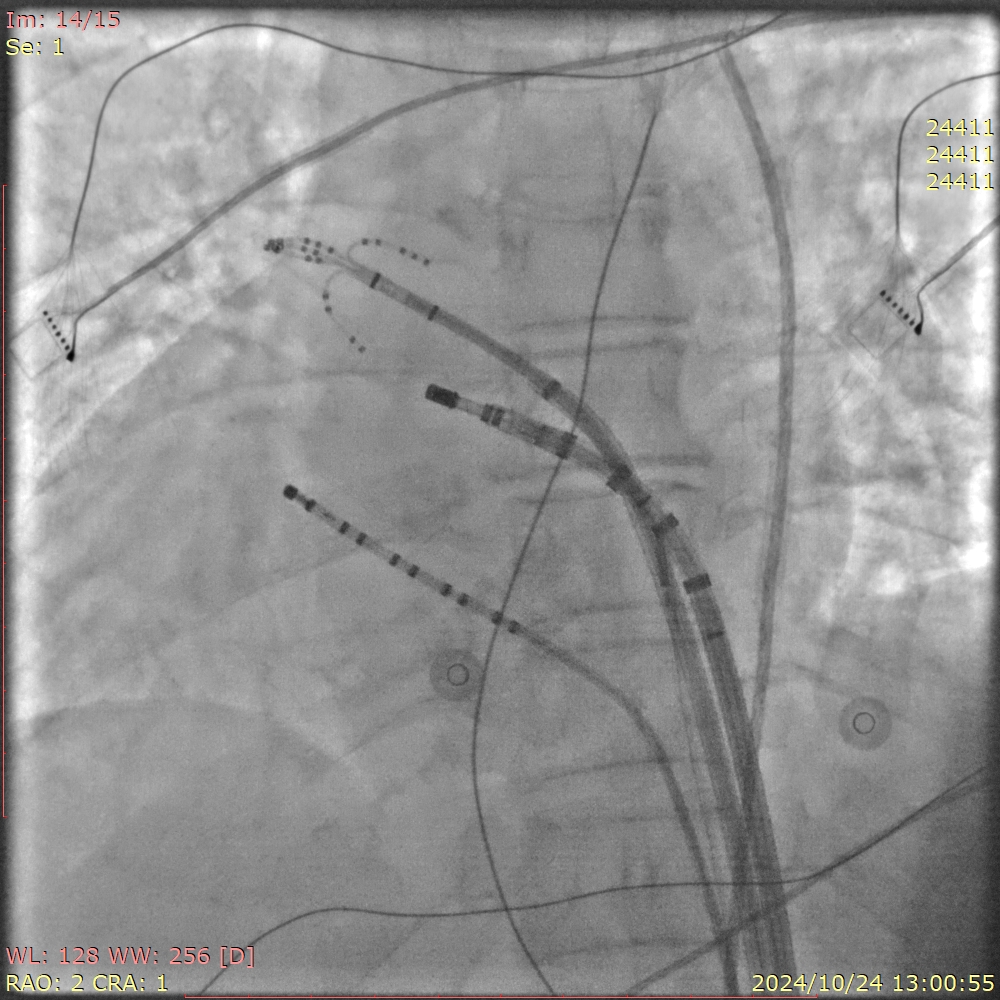

手术过程中,王洪涛教授亲自操刀,充分利用CARTO 3三维标测系统,实现了精准定位和消融,成功为患者实施了房颤射频消融术。随后,团队又克服了镜面右位心带来的操作困难,使用新一代国产左心耳封堵器LACbes成功完成了左心耳封堵术,有效预防了卒中的发生。王洪涛教授解释:“房颤射频消融术能够消除房颤的症状,而左心耳封堵术则能够闭合房颤患者血栓发生的根源部位,两者结合能够大大降低患者的卒中和出血风险。”